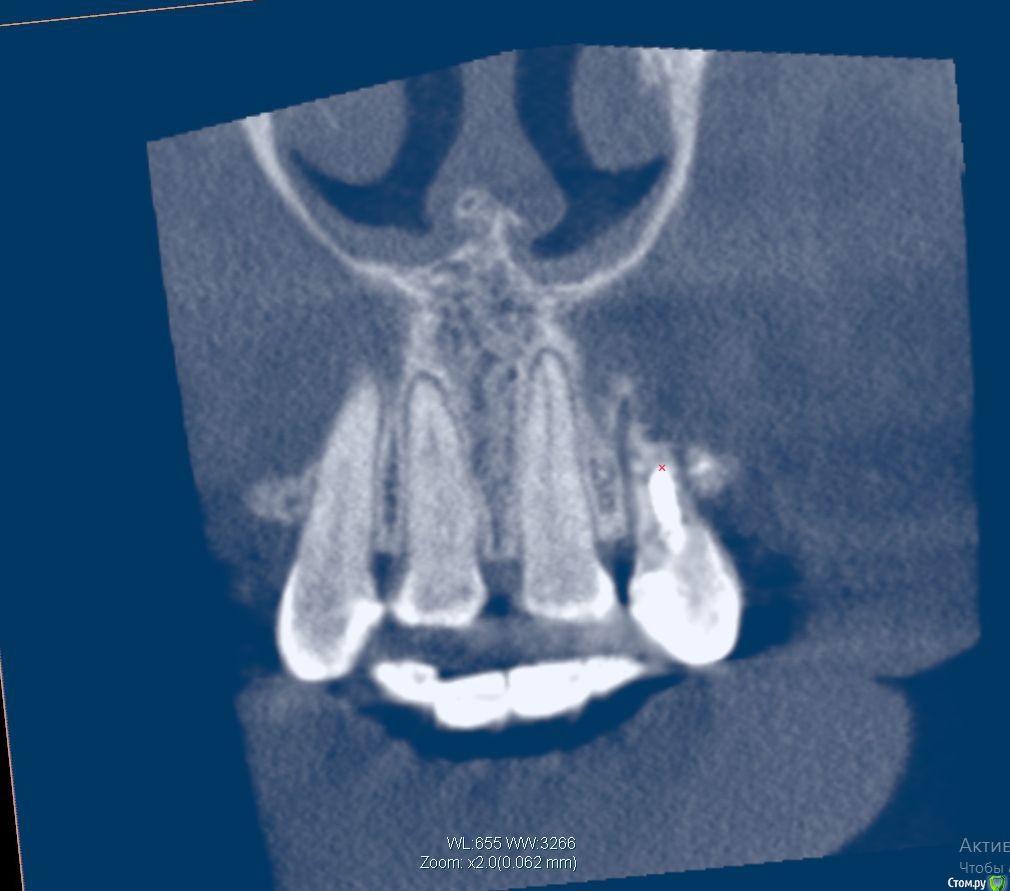

Lanasvlisa Опубликовано 21 апреля, 2017 Поделиться Опубликовано 21 апреля, 2017 Добрый вечер, уважаемые врачи! Вопрос по зубу 22, он леченый-перелеченный, сейчас на корне обнаружена киста, на десне над зубом свищевой ход. Какое ваше мнение: 1) удалять зуб и вместе с ним уйдет воспаление, прочищать все и заниматься имплантацией; или 2) можно каким-то образом удалить кисту, отсечь корень (читала о таком), но сам зуб не удалять? Если всё-таки 1), то можно ли осуществить в данном случае одномоментную имплантацию с нагрузкой? или можно одномоментную, но без нагрузки...? Спасибо огромное всем, кто посмотрит снимки и выразит свое экспертное мнение! С уважением, PS: прикрепляю скриншот из программы, но если этого недостаточно для определения диагноза и плана вмешательства, то скину ссылку на весь архив. Ссылка на комментарий

колесников Опубликовано 21 апреля, 2017 Поделиться Опубликовано 21 апреля, 2017 Резецировать там нечего,во время эндодонтического лечения произошла перфорация стенки корня зуба,вокруг этого участка очаг деструкции костной ткани. Это не лечится.По выставленной вами картинке объём деструкции не понятен. Решить возможность одномоментной имплантации и тем более немедленной нагрузки может только ваш лечащий доктор ,по результатам кт и в соответствии со своим опытом. Ссылка на комментарий

Lanasvlisa Опубликовано 22 апреля, 2017 Автор Поделиться Опубликовано 22 апреля, 2017 Здравствуйте, уважаемые врачи, и спасибо большое вам за оперативные ответы! Я не знаю, как найти срезы, полагаю, проекции - это то же самое, что и срезы? Я сделала их скриншоты+ еще три фото. А если я все-таки отправлю ссылку на весь архив, вы бы могли оценить объем разрушения костной ткани, чтобы предположить, насколько реально провести имплантацию в день удаления? У меня еще такие вопросы: если имплантацию удается провести сразу, то 1) через какой срок можно в моем случае заняться установкой коронки; 2) какая она должна быть; 3) если придется пользоваться "бабочкой" (я так понимаю, это единственный вариант, все временные коронки, в том числе клеевые, - это нагрузка, а каппа сюда тоже не подойдет?), то как потом происходит восстановление формы десны? Можно ли как-то сохранить десневые сосочки в случае отсроченной имплантации? Спасибо большое! Ссылка на комментарий

колесников Опубликовано 24 апреля, 2017 Поделиться Опубликовано 24 апреля, 2017 Полностью поддерживаю. Имплантировать лучше одномоментно и с пластикой десны. Делать отсрочено ,с консервацией лунки,тоже возможно,но мне лично не очень нравится. Если в первом варианте имплант контактирует с вашей костью,то во втором -с искусственной,что иногда приводит к неудачам. Также частенько происходит усадка десны у соседних зубов,исчезает сосочек. Съёмный протез-бабочка только усугубляет эту усадку. Ссылка на комментарий